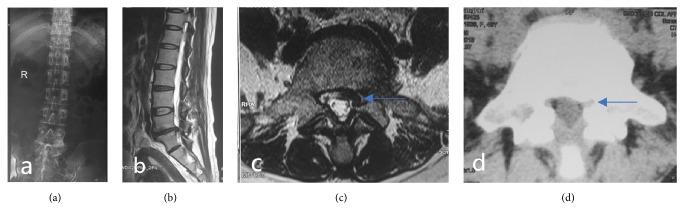

To observe the clinical curative effect of posterior total endoscopic precision decompression for the treatment of single-segment lateral crypt lumbar spinal stenosis (LSS).

A total of 27 patients with single-segment LSS satisfying the inclusion criteria were recruited from July 2013 to September 2015. There were 18 cases of unilateral stenosis of the L segments and 9 cases of unilateral stenosis of the L-S segment. All patients were treated via the posterior approach with the precise lateral crypt decompression technique. Precise decompression was performed on the narrow areas causing clinical symptoms. Clinical efficacy was assessed at 3 days, 3 months, 6 months, and 2 years after surgery. Low-back pain and sciatic nerve pain assessed by visual analog scale (VAS) score and the functional Oswestry Disability Index (ODI) were used to evaluate lumbar function, and modified MacNab score criteria were used to investigate long-term efficacy.

All patients completed the operation successfully, and the follow-up time was 2 years. The VAS score of lumbago was lower after than before surgery (preoperative: 6.96±0.90; postoperative: 2.04±1.02, P<0.05). The VAS score of sciatica was also lower after than before surgery (preoperative: 7.19±0.88, postoperative: 1.93±0.92, P<0.05), and the ODI was improved at the last follow-up (29.62±4.26) % compared with before surgery (80.07±3.98) %. The MacNab efficacy evaluation showed improvement at the end of the follow-up period: 20 cases were excellent, 6 cases were good, and 1 case was satisfactory, with a good/excellent rate of 96%. No surgical site infections, iatrogenic nerve root injuries, epidural hematomas, or other complications occurred.

Total endoscopic decompression of posterior facet arthrodesis for the treatment of single-segment lateral crypt LSS has the advantages of safety, reduced recurrence and trauma, and a satisfactory curative effect. This trial is registered with ChiCTR1800015628.